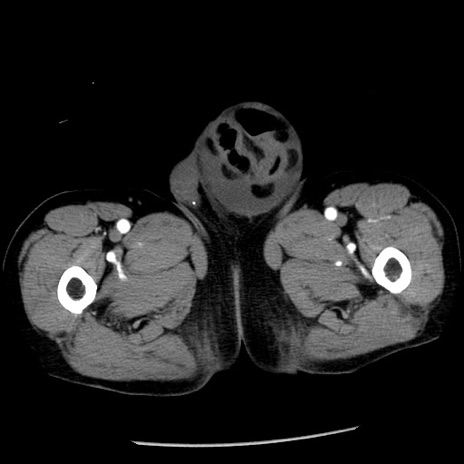

症例26(横断像)

【症例】80歳代男性

【主訴】嘔吐

【現病歴】昨晩2回嘔吐あり、今朝になっても嘔吐あり。来院。

【既往歴】胃潰瘍

【身体所見】意識清明、BT 37.6℃、BP 166/95mmHg、HR 100bpm、SpO2 97%、腹部:平坦・軟、腸蠕動音聴取良好、圧痛なし。

【データ】WBC 21900、CRP 1.46